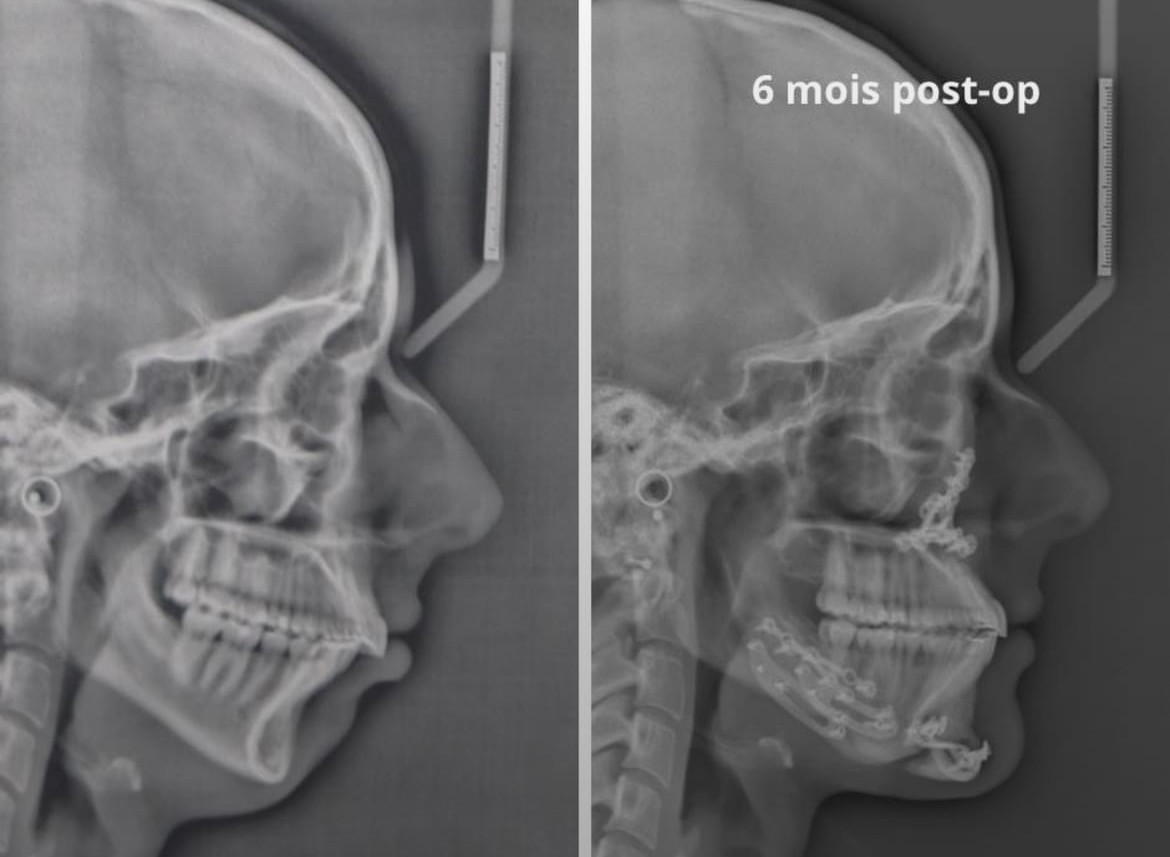

It’s weird cuz she said only 2mm Lefort and 2mm BSSO, I guess the genio combined with giga CCW carried the resultdo you know her movements?

she had a minor maxilla setback. surgeon didnt want to perform impaction which can lead to breathing problems i assume. posterior downgraft, good bsso and genioIt’s weird cuz she said only 2mm Lefort and 2mm BSSO, I guess the genio combined with giga CCW carried the result

View attachment 4600008